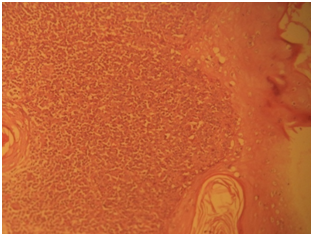

Gross examination showed fragments of gray, white tissue partly covered by skin aggregating 1.8cm. Histological sections showed ulcerated skin tissue exhibiting intradermal monomorphic lymphoid cells infiltrating the epidermis and the adipose tissue (Figure 6) (Figure 7).The cells have round to oval nuclei with the moderate amphophilic cytoplasm. Quite a few cells that have vesicular nuclei with the cerebroid nuclear pattern were noted. Focal areas showing pautriers microabscesses were also present and there is low mitotic activity (Figure 8). The overall features are consistent with Mycosis fungoides.

Figure 8 Photomicrograph shows the pautriers micro abscess, H and EX100.